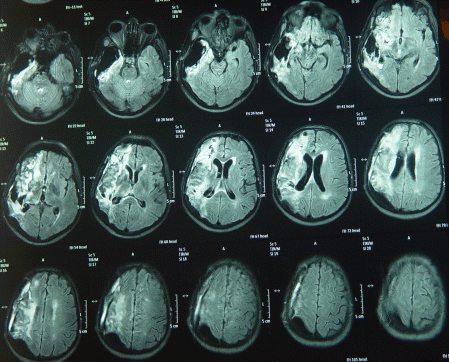

The patient showed steady improvement and the tracheostomy was removed 15-December-2007 and started normal feeding and MRI performed 23-December-2007 showed halt of the aggressive growth of the tumor.

The last picture showing the right MCA eaten by the tumor, despite anatomical preservation during surgery.

The patient underwent radiotherapy, and MRI done 17-Maech-2008 showed no signs of recurrence, still bedridden and can eat well and some times talking and responding to verbal stimuli.

MRI repeated 18-August-2008  showing of the other left hemisphere and involvement of the brain stem in the right side. with deterioration of his condition.

MRI done 04-December-2008 showing enlargement of the right sylvian mass location and down to the vermis. He is completely bedridden and to my knowledge he died 3-4 months later.